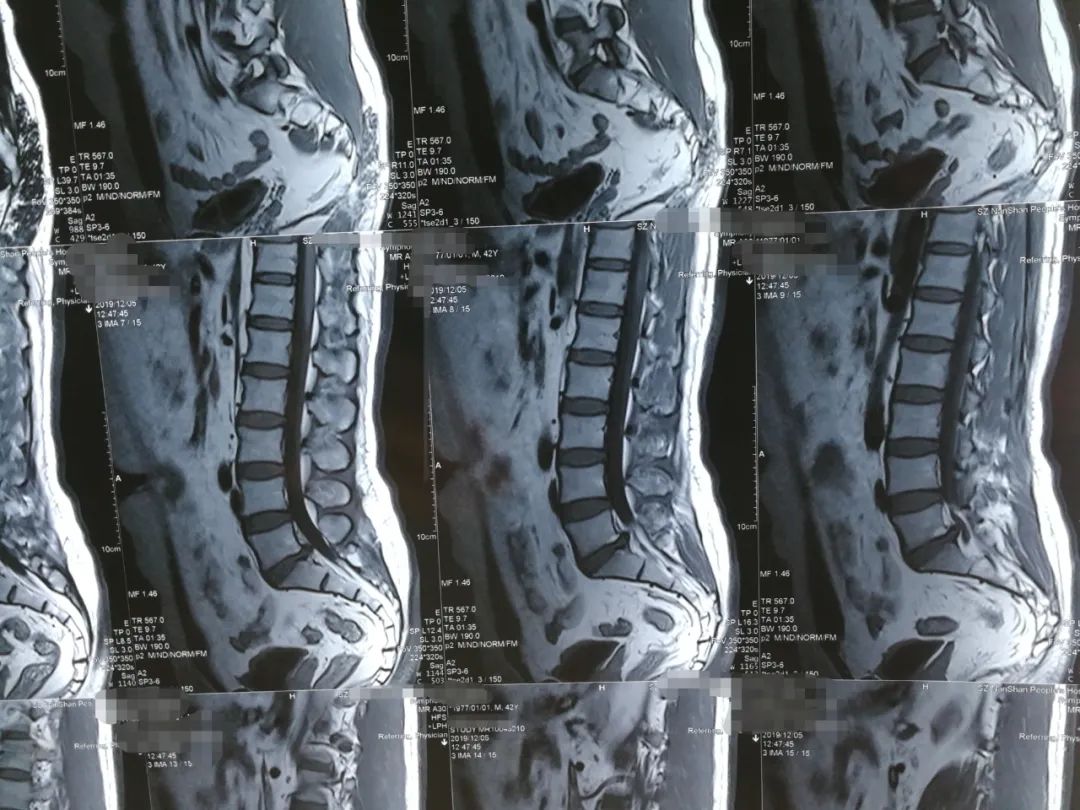

阅片

刘先生是典型的“腰椎间盘突出症(L5S1左后突出)”,伴有椎管狭窄的间歇性跛行症状,专科查体时最主要的体征是:

1、L5S1棘突左侧旁开1厘米处压痛、叩击痛并反射至左小腿后侧(骶1神经支配区);

2、仰卧挺腹试验未完成(因为疼痛);

3、左侧跟腱反射消失(骶1神经受压所致)。